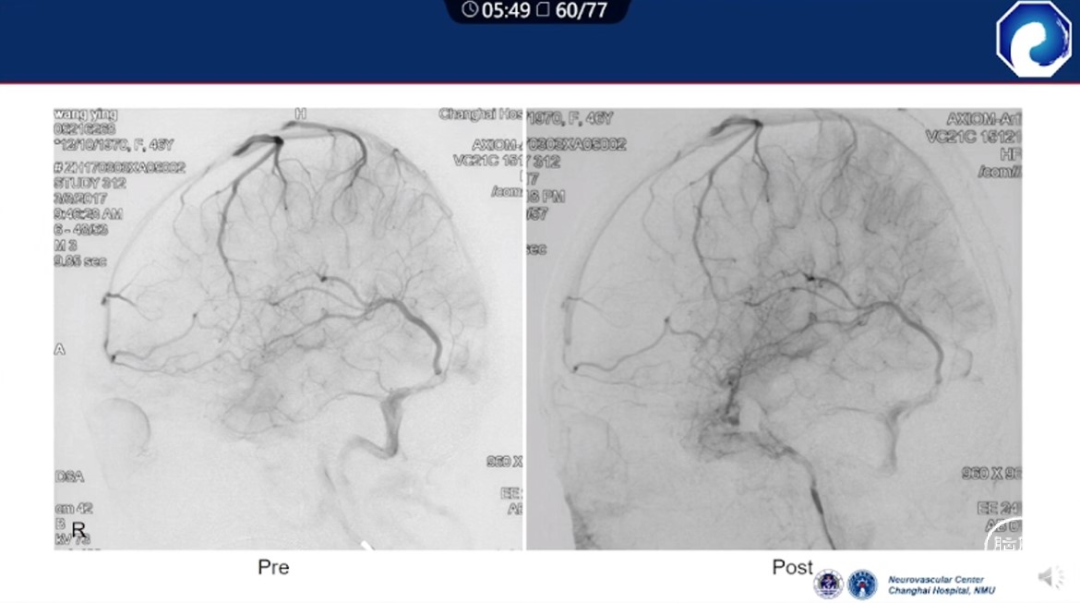

痿口静脉端精准完全闭塞是DAVF治愈的关键。

靶向性栓塞可以减少海绵窦分隔的过渡栓塞,有利于减少颅神经并发症,恢复海绵窦的正常引流功能。

减少栓塞材料应用。

减少与颈内动脉重叠,避免栓塞材料意外栓塞。